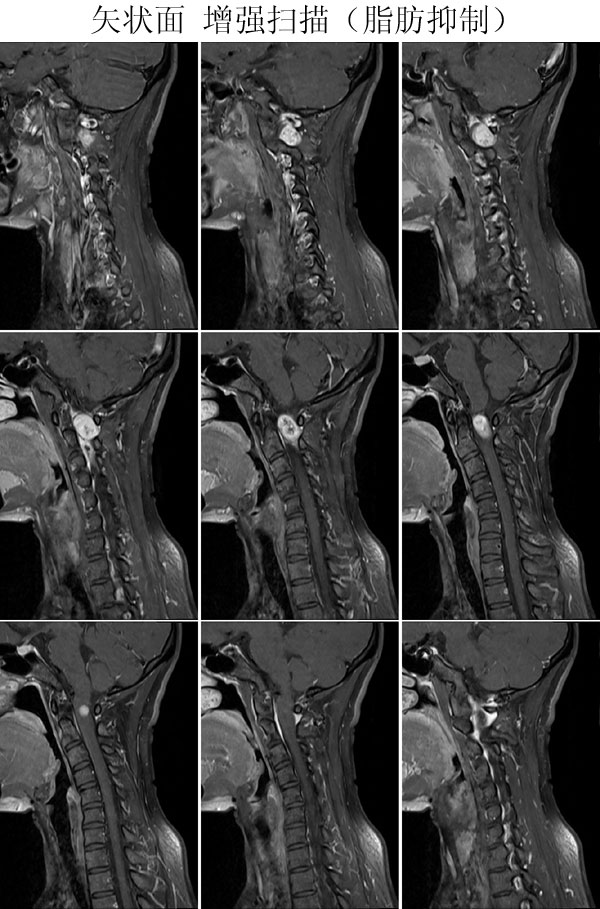

本病例来自广东同江医院

病史:女,27岁,洗头按摩时扭颈导致昏迷,检查发现颈椎占位

手术病理:

神经鞘瘤